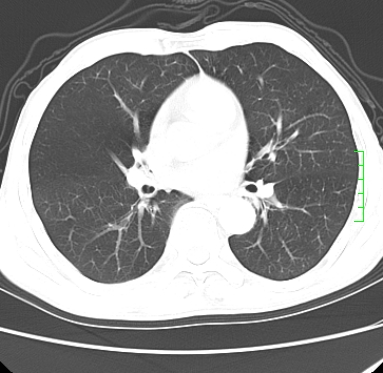

m,73y。膝关节疼痛伴双下肢水肿。入院常规胸片发现结节灶。增强为静脉期。

浅分叶、棘突,考虑右下肺周围型肺癌

考虑周围型肺癌  ,双上肺结核。

肿块周围可见局限性气肿,考虑肺癌可能性大。双肺上叶继发型肺结核。

指套征,强化明显,近侧肺组织局限性肺气肿,考虑支气管类癌,慢支、肺气肿、双上陈旧性tb、冠脉钙化。

鉴别:先天性支气管闭锁,变态反应性支气管肺曲霉菌病,肺癌,支气管囊肿,支扩黏液嵌塞。

1)考虑右肺下叶周围型肺癌。2)右肺上叶及左肺感染性病变(结核可能)。3)肺气肿。4)冠状动脉钙化。